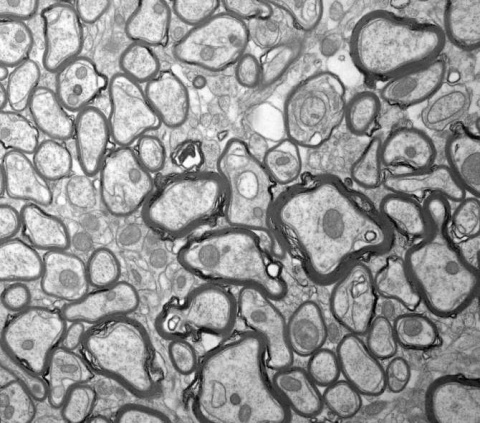

![[Img #61557]](https://noticiasdelaciencia.com/upload/images/08_2020/1120_contaminacion-del-aire-y-salud-respiratoria-infantil.jpg)

Zona industrial. (Imagen: Amazings / NCYT)